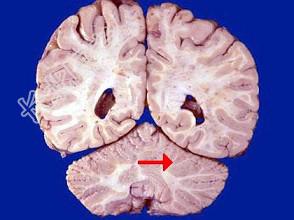

- 单项选择题如图箭头所示为颅脑哪个部位 ( )

A、顶叶

B、枕叶

C、小脑

D、脑干

E、额叶